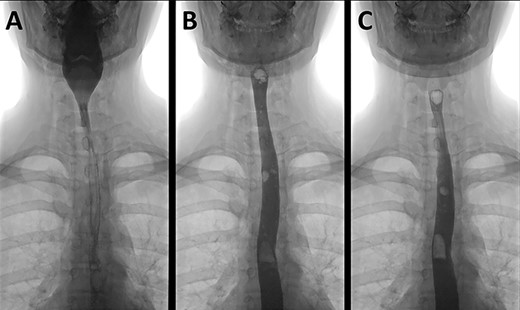

On initial assessment, pneumoderma was palpable on the anterior chest wall and neck. Blood tests revealed a haemoglobin level of 176 g/L (normal range 110–150 g/L) and white blood cell count of 17.71 × 109/L (normal range 3.5–11 × 109/L). Serum urea and creatinine were mildly raised from her baseline. The C-reactive protein level was 7 mg/L (normal range < 5 mg/L). These results were largely explained by dehydration secondary to prolonged vomiting. A chest radiograph (Fig. 1) revealed extensive surgical emphysema and pneumomediastinum.

A chest radiograph illustrating surgical emphysema and pneumomediastinum.